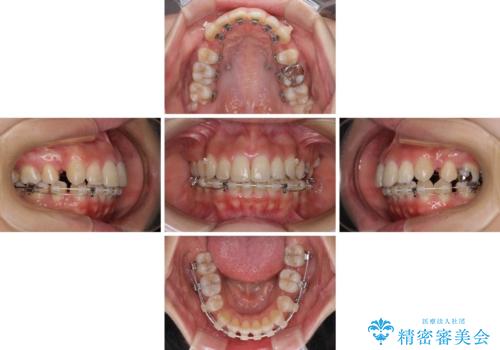

突出した口元が気になる ハーフリンガル装置による抜歯矯正

- 口元の突出感を気にして来院された患者様です。

通常では上下左右の第一小臼歯4本を抜歯しますが、下顎が左側にシフトしていたため、下顎左側のみ第二小臼歯を抜歯し、正中を合わせながら口元を下げる治療計画としました。

ハーフリンガルは、通常では表側のワイヤー矯正よりも治療期間がかかります。特に今回のように下顎左側をイレギュラーの第二小臼歯抜歯としたため、さらに時間がかかることが予想されました。

実際に治療をおこなってみると、2年を切る短期間で治療を終えることができました。